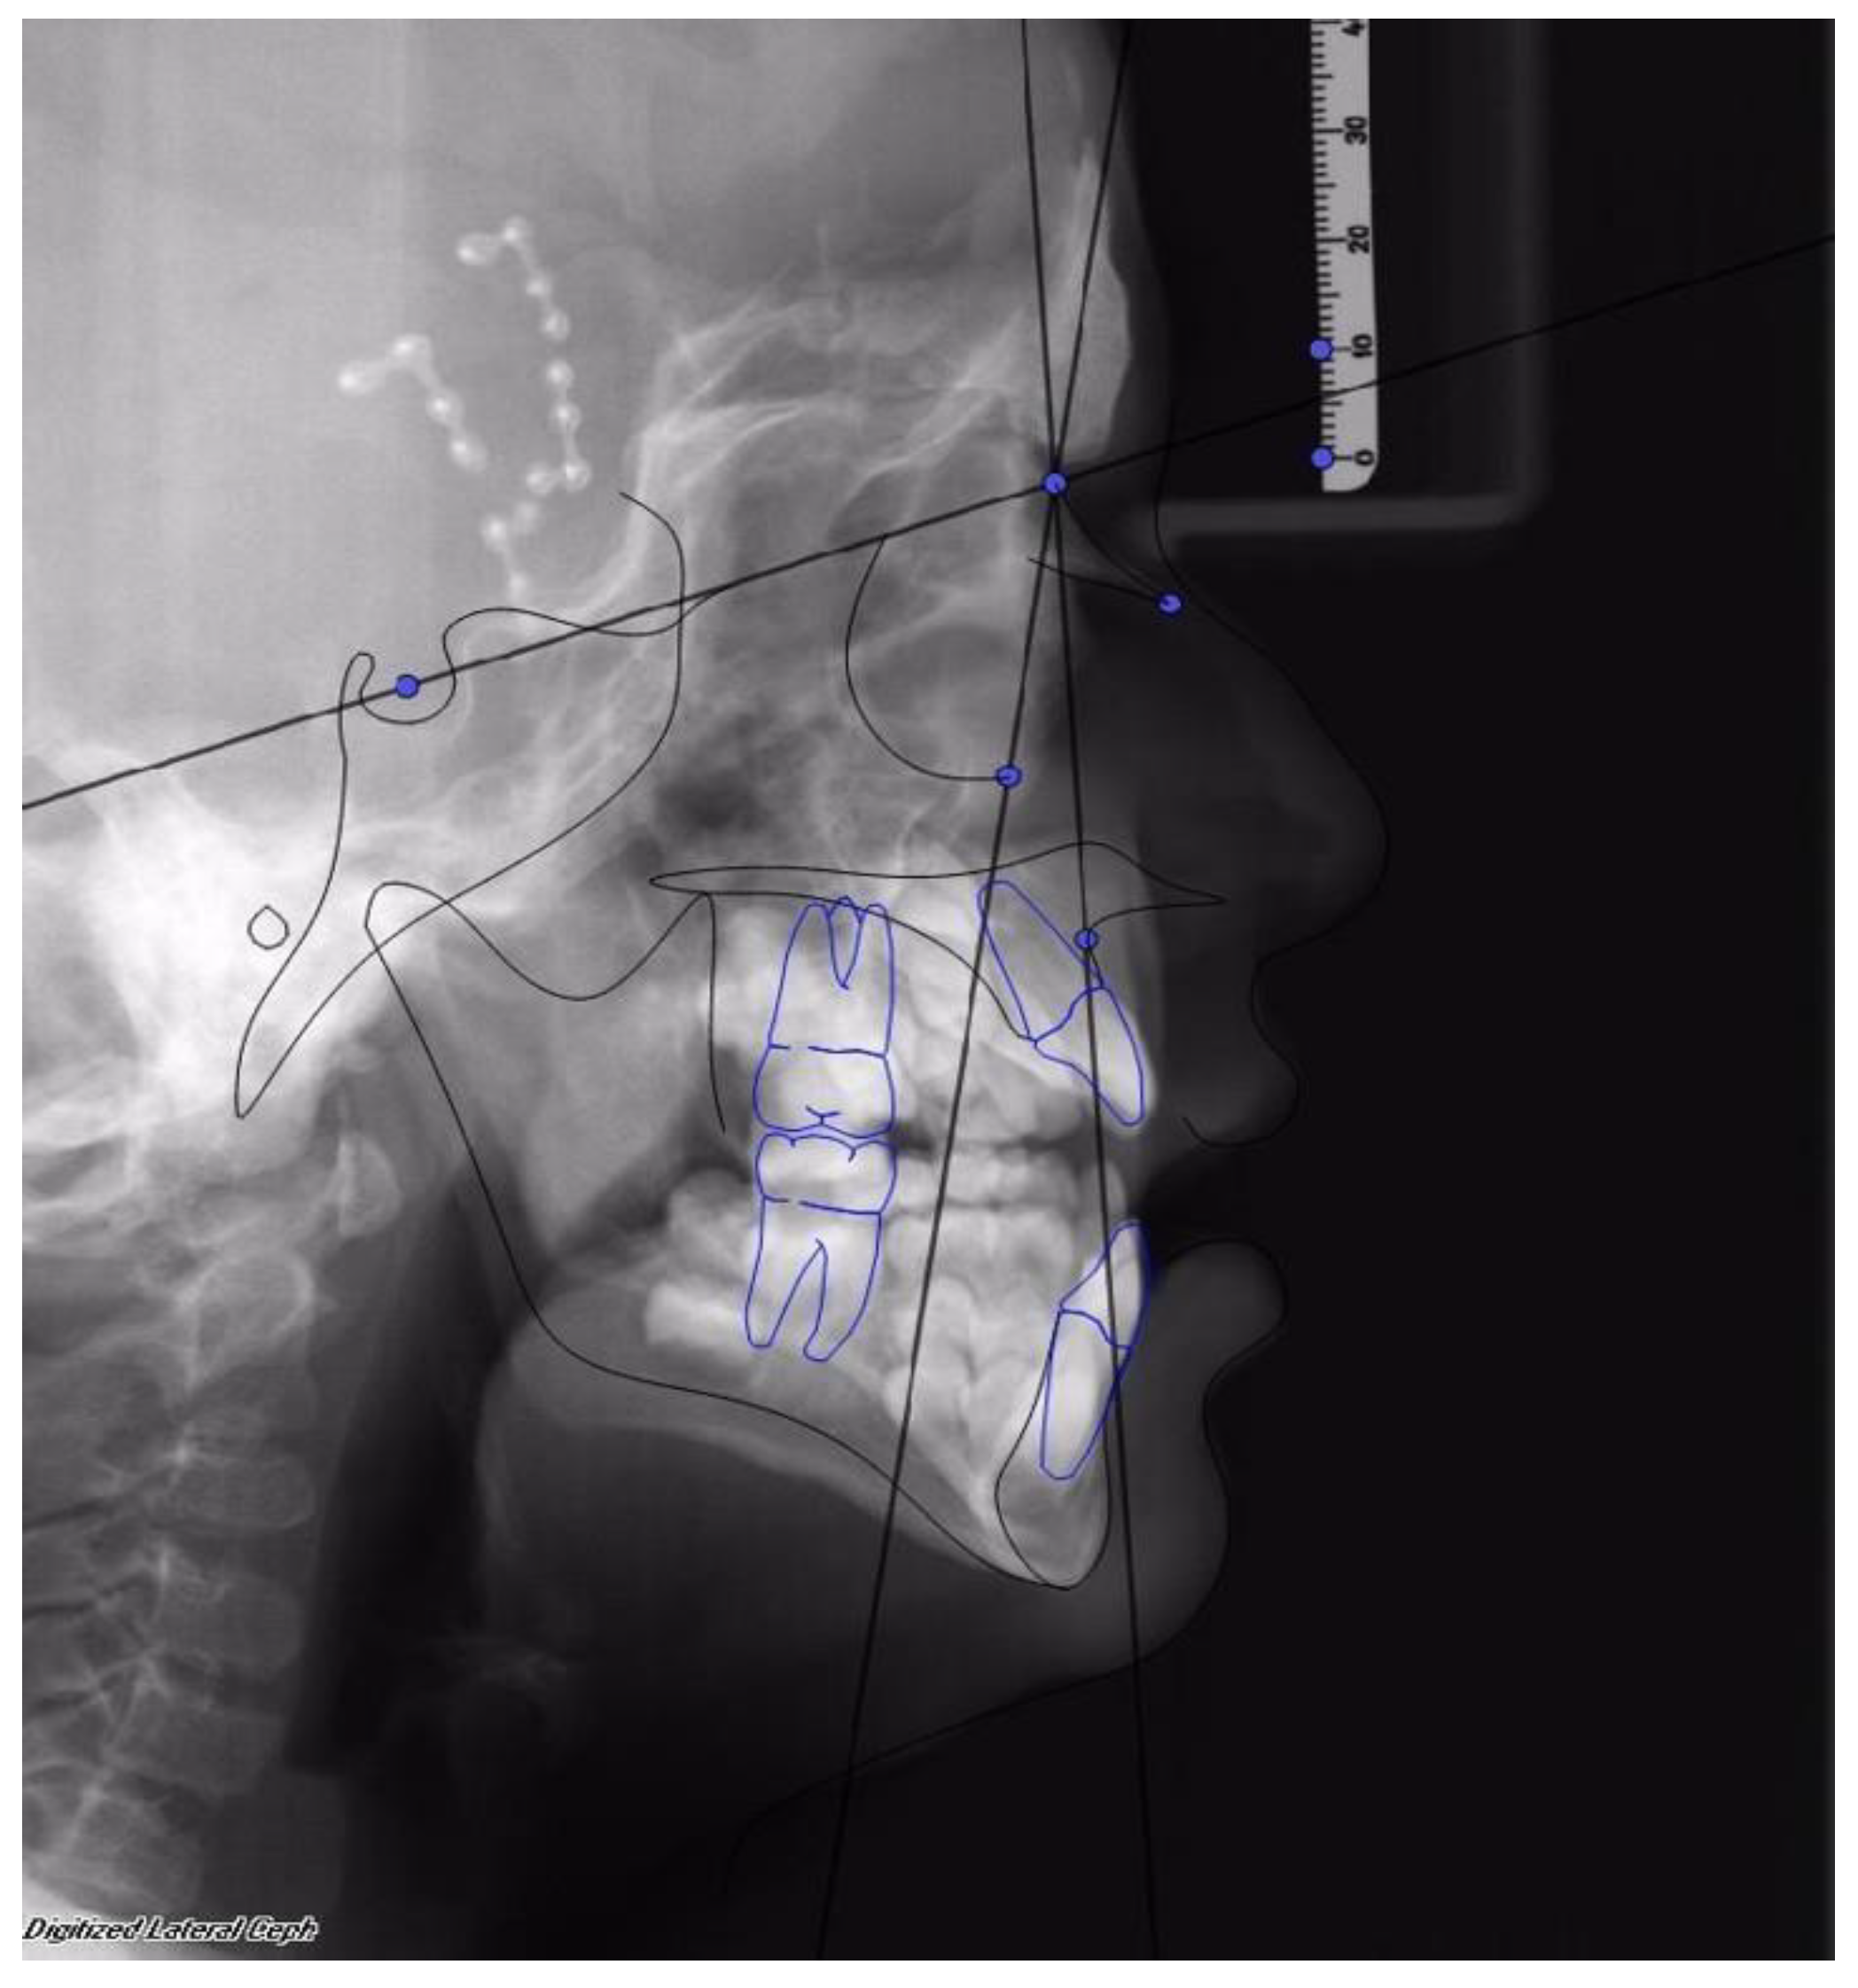

Facial advancement was satisfying for every patient, only the advancement of patient 1 should have been greater in order to reach the appropriate projection. Clinical results were anyway satisfying, so no further surgical procedure was undertaken. (See Figure 2 and Figure 3).

Figure 3. The same patient after 1 year from the end of treatment with MAC. SNA was 76° and SNOr was 63°.